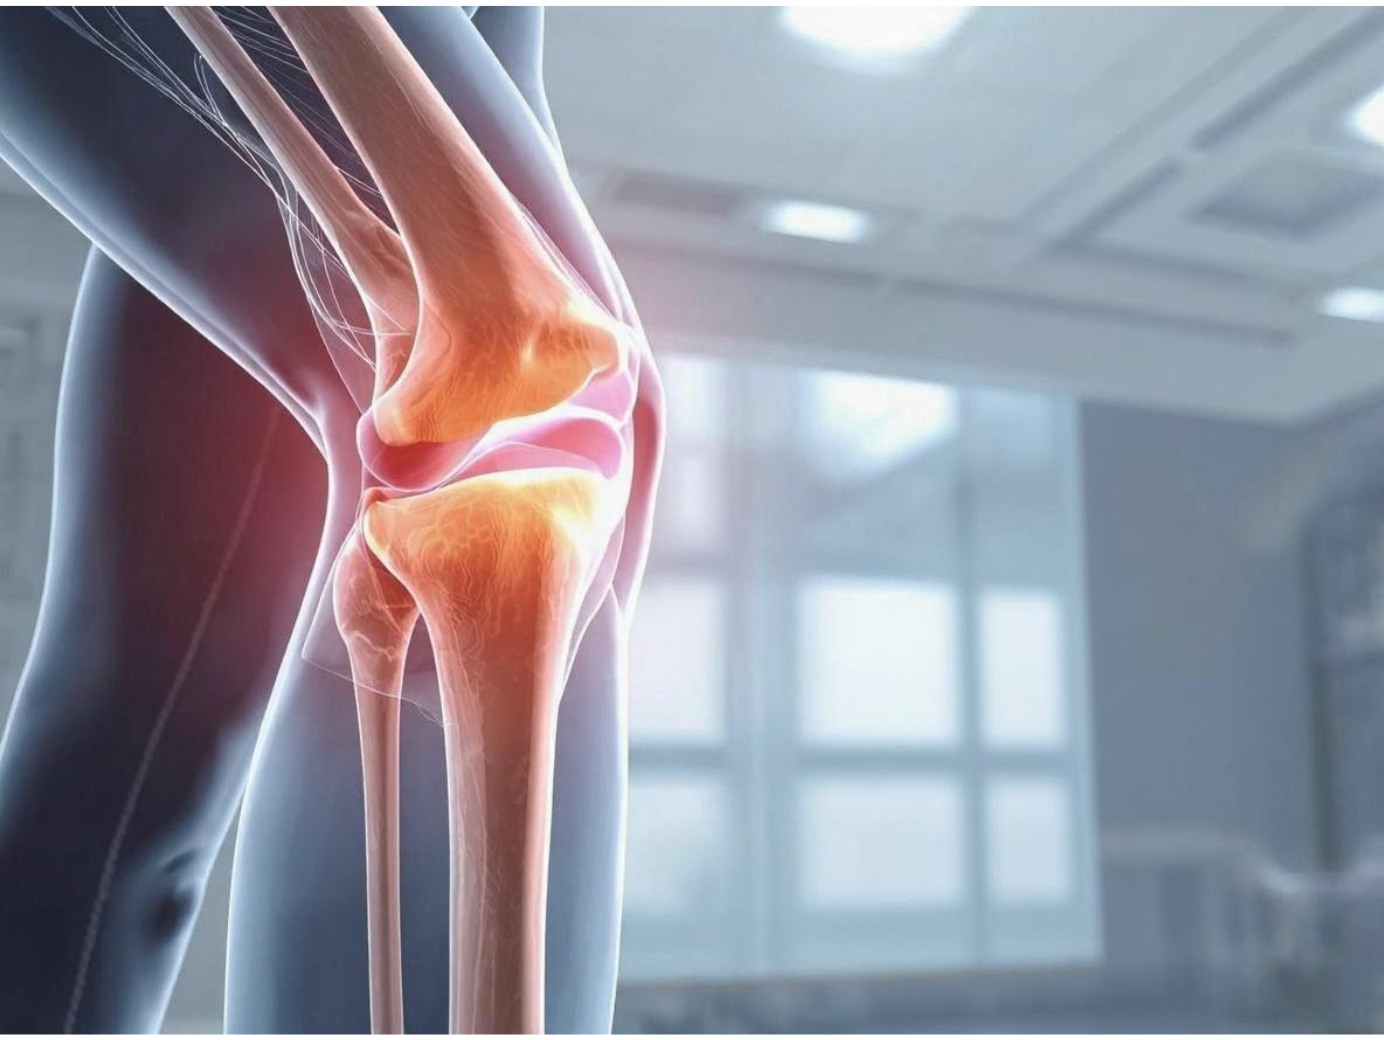

تُعد آلام الركبة من أكثر المشكلات العضلية الهيكلية شيوعًا، وهي سبب رئيسي يدفع الكثير من الأشخاص إلى زيارة الطبيب، نظرًا لما تسببه من إزعاج وتأثير على الحركة اليومية.

يشير الشعور بألم في الركبة في الغالب إلى وجود مشكلة صحية أو إصابة معينة، ويختلف شكل الألم وحدته حسب موضع الإصابة. فقد يبدأ الأمر بانزعاج بسيط، ثم يزداد تدريجيًا مع مرور الوقت إذا لم يتم التعامل معه بالشكل الصحيح.

الام الركبة هو الشعور بالألم أو الانزعاج في مفصل الركبة نفسه أو في المنطقة المحيطة به. وتُعد الركبة أكبر مفصل في جسم الإنسان، ولهذا فهي من أكثر المفاصل عرضة للإصابة والمشكلات المختلفة.

ومع تكرار هذه الحركات، يتعرض مفصل الركبة لضغط مستمر، مما قد يؤدي إلى الشعور بألم عند الثني أو الفرد، خاصةً في حالة وجود مشكلة في الأوتار أو العضلات أو الأربطة أو الغضاريف المحيطة بالمفصل.